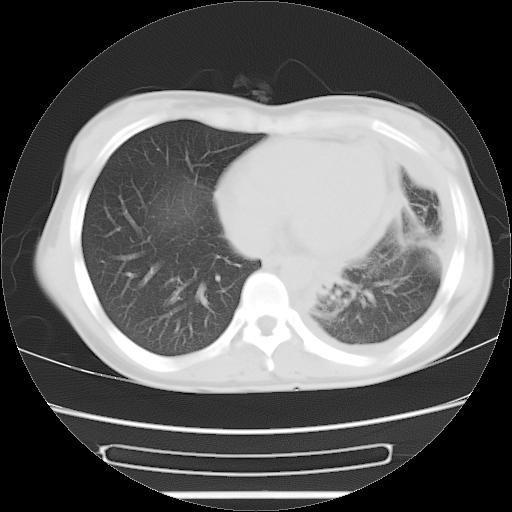

标题: CT21561:外院胸片提示胸腔积液,行CT检查。 [打印本页]

女,29岁,胸部不适,在外院胸片提示胸腔积液,到我院ct检查。

肺窗:

1、左侧包裹性积液伴叶间积液 2、右肺多发结节考虑增殖结节

左肺上叶不张,左侧胸水,叶间裂积液,纵隔淋巴结,脾脏钙化,考虑左肺上叶支气管内膜结核,结核性胸膜炎,脾结核

考虑:1.两肺tb;2.左侧胸膜炎、胸腔积液。

考虑两肺结核,左侧包裹性积液,叶间积液。

支持两肺继发性肺结核,左侧胸膜腔包裹性积液、胸膜肥厚,脾内多发钙化(结核钙化)。

右肺多发结节。左胸腔多发包裹性积液。